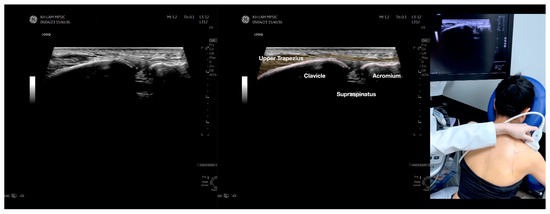

Figure 2.

Sonoanatomy of the lateral border of the inferior trapezius, its related muscles, and the infraspinatus fascia. The step-by-step scanning techniques of the structures illustrated in this figure have been shown in Video S6. Available online: https://www.dropbox.com/s/vjj49wiwdsidouz/Figure%202.docx?dl=0 (accessed on 1 January 2023). Dynamic ultrasound scanning of the anterior shoulder with the humerus externally rotated (palm up), elbow straight, and the shoulder actively flexed and abducted at about 90 to 100 degrees shows that the fibrotic and thickened bursa was noted to be snapping between the subscapularis tendon and the coracoacromial ligament, as shown in Video S3. The patient noticed this snapping during many of his daily activities with his shoulder flexed just above 90 degrees, e.g., taking off clothes and combing hair. Ultrasound-guided injection of the thickened and fibrotic bursa did not reproduce the usual pain nor reduce the pain, and it did not improve the shoulder snapping and flexion power with the elbow straight, shoulder flexed to 90°, and the humerus externally rotated (palm up). Ultrasound-guided injection of the cortical break reproduced the concordant pain and temporarily and partially reduced the pain with snapping and residual anterior shoulder pain (Video S4), but it did not change the snapping or weakness in the right shoulder flexion with the humerus in external rotation. With the failure of direct anterior treatment to the suspected lesions, it was essential to further explore other causes for the anterior painful snapping. Further detailed musculoskeletal examination of the scapular movement showed that the right scapulothoracic movements were not smooth compared to the left counterpart (Video S5) [4,5]. There might be some disruptions in the right infraspinatus fascia (IF) and its related muscles, including the lateral edge of the right inferior trapezius, rhomboid minor and major [6], teres major, latissimus dorsi [7,8] (LD), and posterior deltoid attachments to the IF [9,10]. Clinically, prominent and active trigger points were observed in the right infraspinatus muscle. Holding the inferior angle of the scapula, with the examiner’s fingers, especially over the origin of the teres major muscle over the scapula, the latissimus dorsi [11,12,13] and the scapular insertion of the rhomboid major muscle significantly improved the power of the resisted shoulder flexion with the elbow straight and the shoulder flexed to 90° with the humerus externally rotated (palm up). In order to illustrate the utilization of ultrasound-guided sonopalpation and ultrasound-guided digital palpation for detecting the suspected lesions of the IF and its related muscles, we presented the following videos (Videos S6–S9) and still images (Figure 2, Figure 3, Figure 4 and Figure 5) to demonstrate the essential techniques and crucial points of getting the normal sonoanatomy of the IF and its related structures. The gross anatomy of the IF and its related muscles were also shown in Figure 6, Figure 7 and Figure 8.